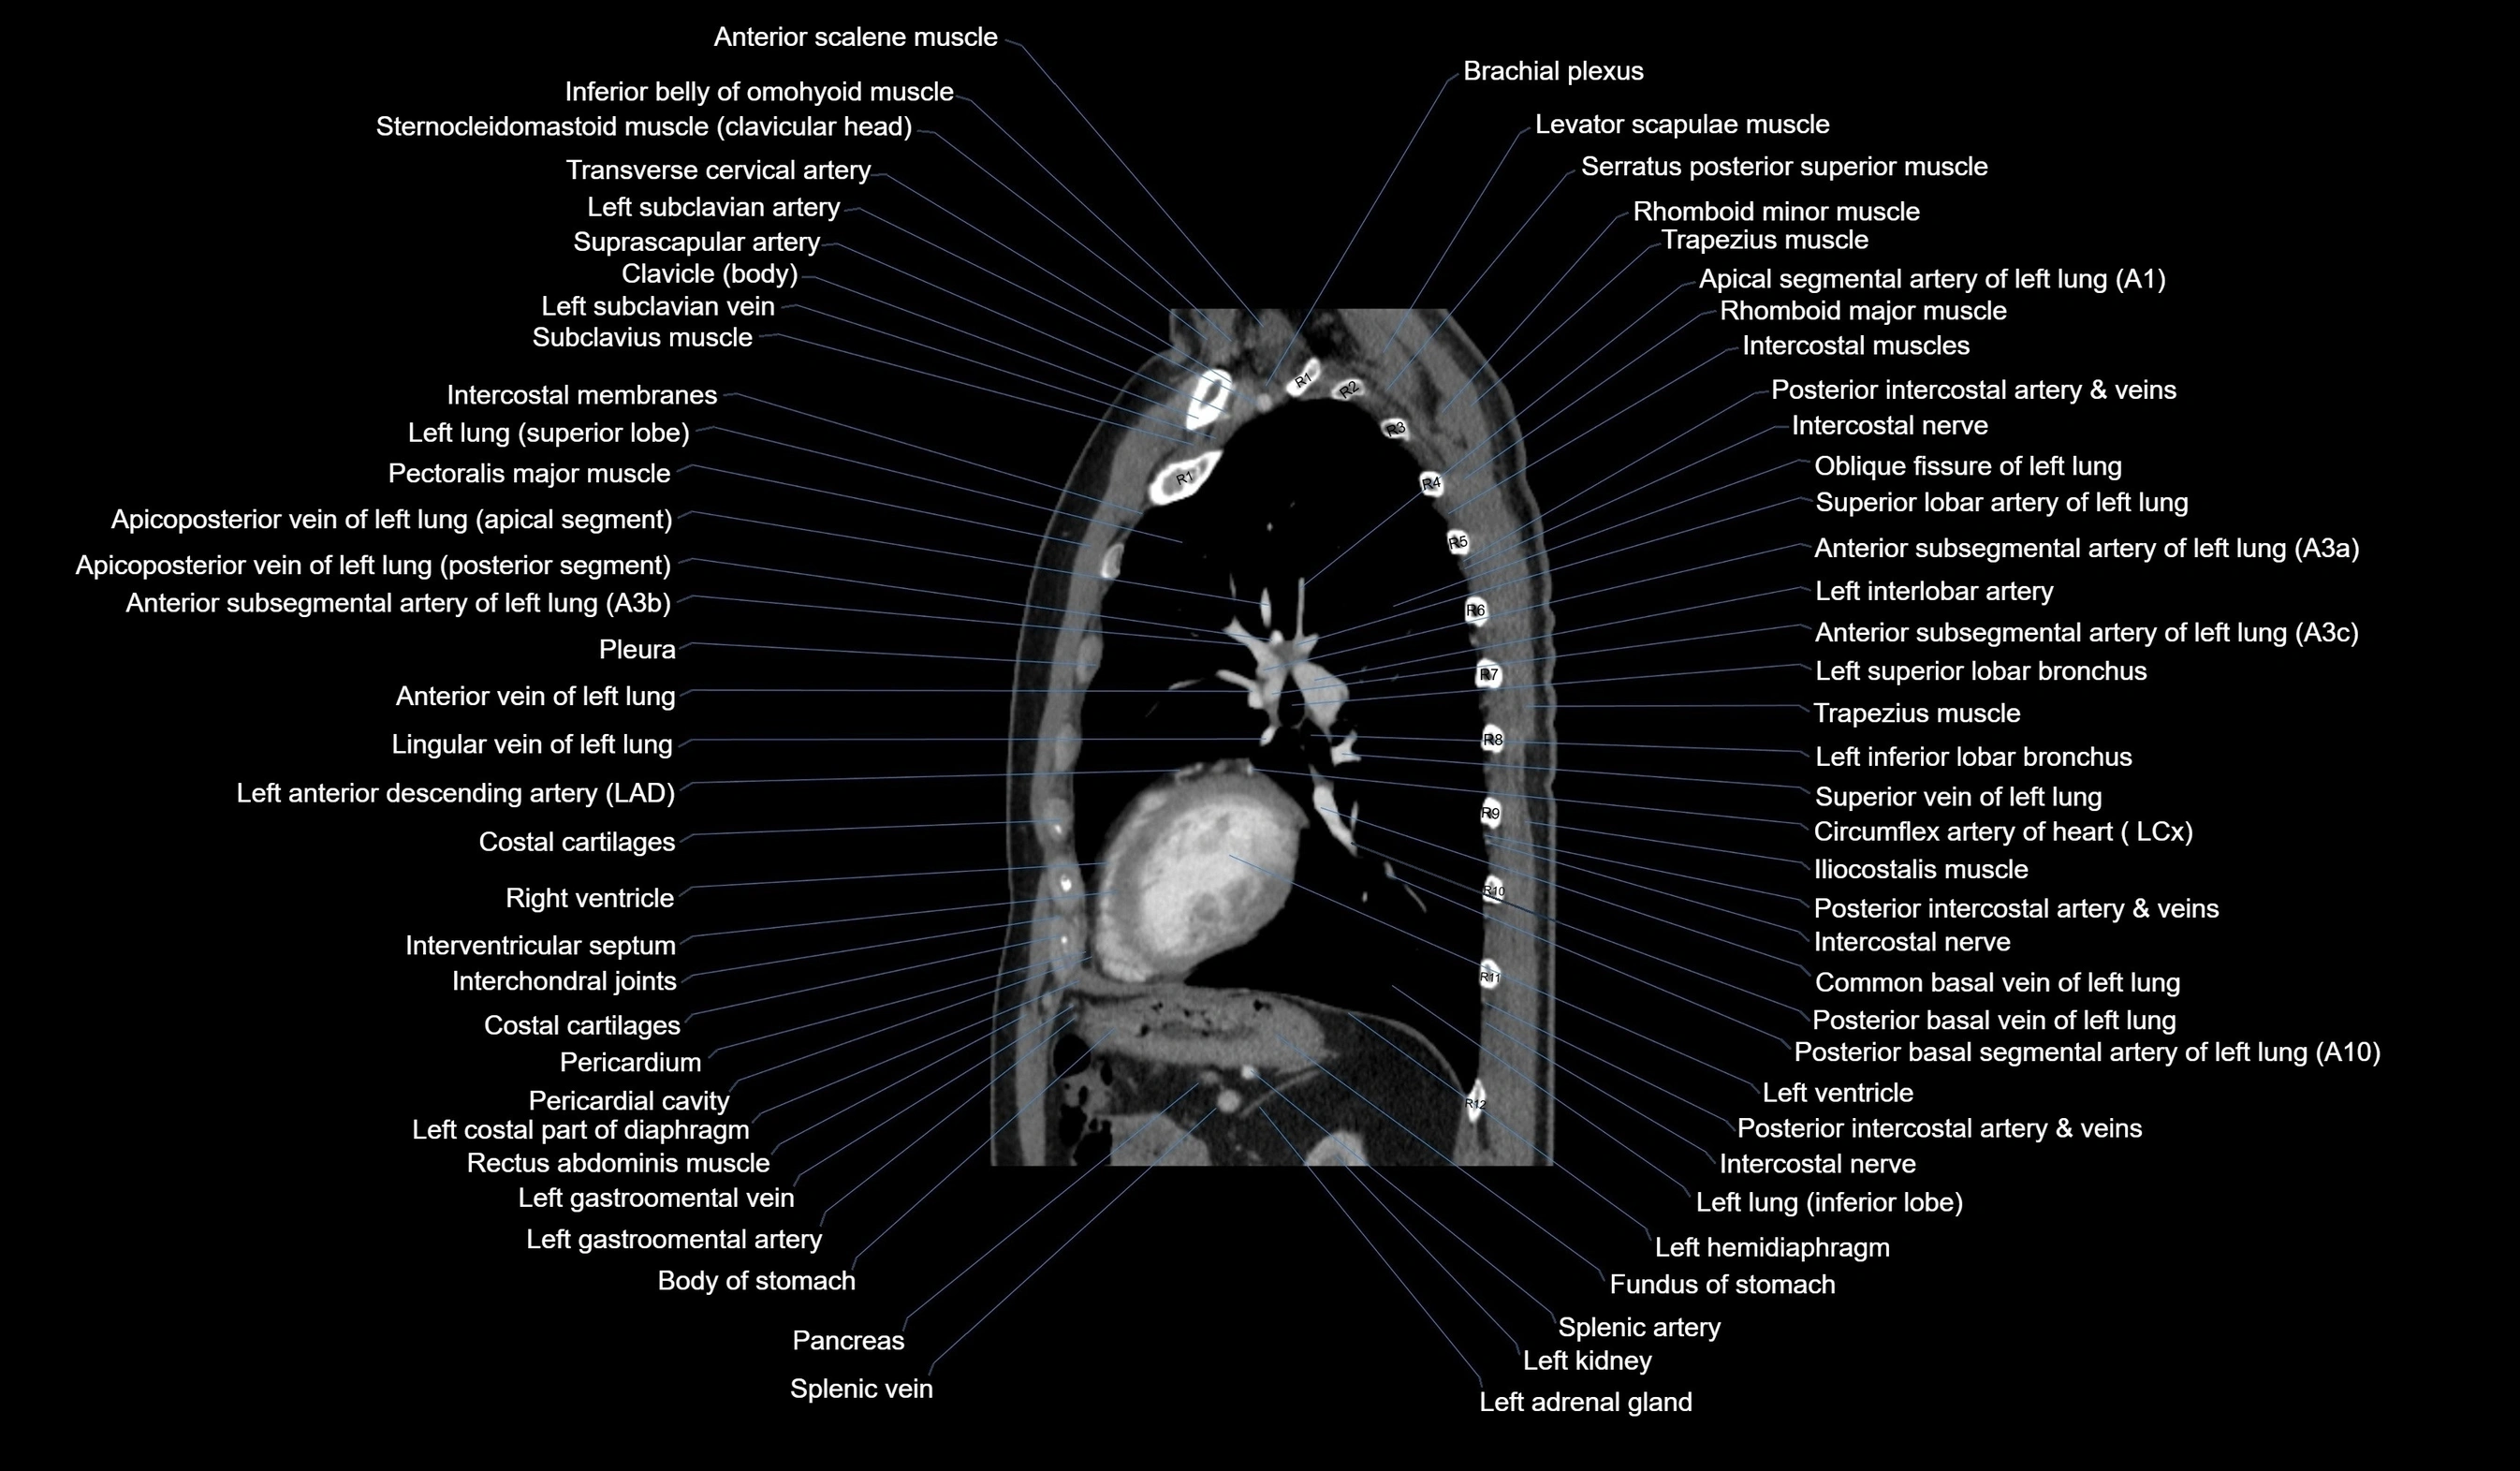

CT images